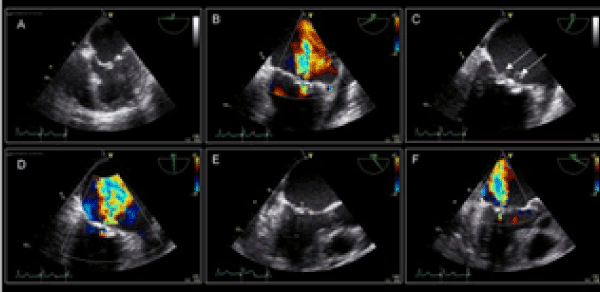

Dilated right chambers with signs of pulmonary hypertension, with distension of the pulmonary artery are found. Dilated veins cavas. The mitral valve, with great commitment of the posterior leaflet, with vegetation 2 × 2 cm, with perforation of the entire valve with severe insufficiency, fragility and engagement ring to the back is severely inadequate.

These findings conditional are not able to perform a mitral valve plasty and opt for a change with aortic mechanical prosthesis placed in the mitral position given the cardiac size do meter fitting a ring on aortic -× 21 mm and decided to place an aortic valve mitral invested in position (Figures 2-5).

Figure 2. Mitral valve endocarditis.

Figure 3. Mitral valve endocarditis